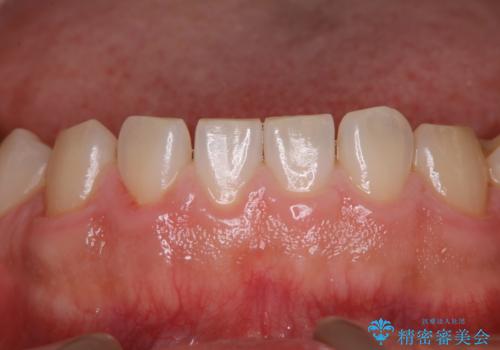

20年ぶりのクリーニングということもあり、歯の表面全てにプラークが付着していました。

プラークの細菌によりかなり歯ぐきが腫れていました。1度のクリーニングで汚れは落とせますが、このまま何もしないとまた同じようにプラークが付着し、それを繰り返すことになるだけでなく、歯周病や虫歯が進行してしまいます。そうならないためには、日々のケア、ホームケアがとても大事になっていきます。